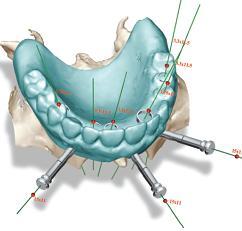

A custom designed surgical template is created, based on our exact planning. We know the final position of the implants before we start. This allows the laboratory to make the prosthetic solution beforehand, so it can be delivered to the patient during the actual surgery.

The multi-faceted nobelGuide concept adapts to any level of practice. We can still work with conventional model-based planning. Or we can plan digitally, using the NobelGuide software powered by Procera , which gives a perfect view of patient's anatomy.

With NobelGuide™ the placing of the implant, abutment and restorative crown or bridge is simultaneous. It is applicable to any patient indication, by using either conventional modeling or computer aided-3D design – NobelGuide™ shows you the exact position and depth of the implants before surgery.

This information enables Nobel Biocare to produce a surgical template which guides the flapless procedure from start to a completely successful placement.